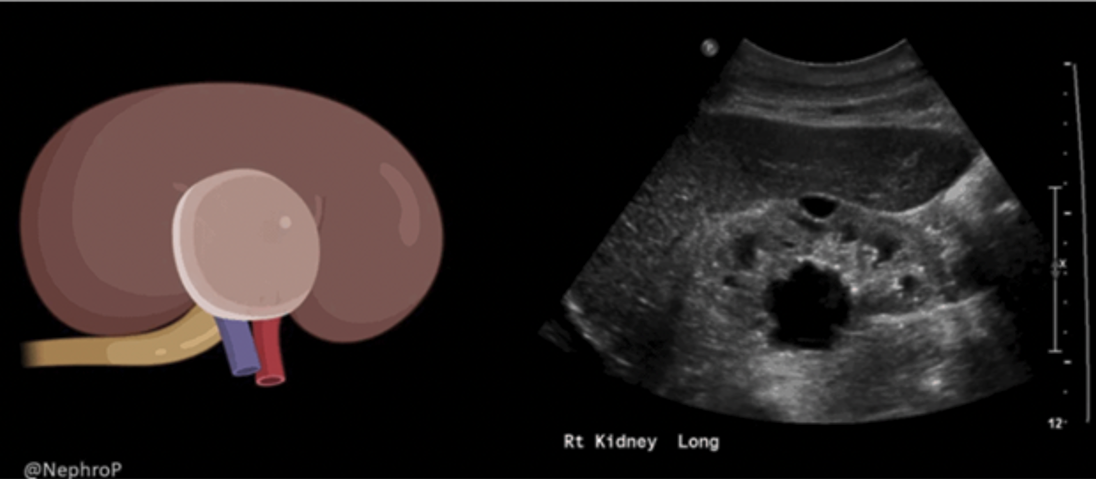

A common limitation when assessing cardiac function is foreshortening of the ventricle, particularly in the PLAX and A4C views (Figure 28,29). Foreshortening occurs when the imaging plane cuts through the heart at an angle that misses the true apex, making the LV appear shorter and more rounded than it actually is. This leads to underestimation of LV size, overestimation of LVfx and poor visualization of true wall motion. To minimize this, adjust your probe position, often one intercostal space lower, if you notice a truncated LV. That said, in some patients, a foreshortened view may be the only achievable window due to body habitus, lung interference, or cooperation. In such cases, it is essential to recognize the limitation and interpret findings with caution. This is why the heart should always be imaged in as many views as possible.

Figure 28: Comparison of PLAX foreshortened VS not foreshortened.

Figure 29: Comparison of A4C foreshortened VS not foreshortened